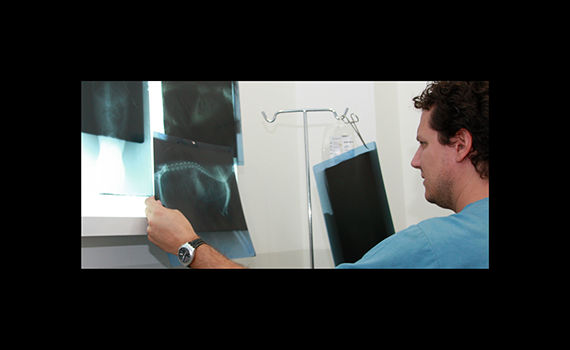

radiología

La radiologia es imprescindible en traumatologia y en algunos diagnosticos, ya sea mediante radiologia simple ó de contraste.

traumatología

En clinican podemos tratar las diversas afecciones que pudan afectar a huesos y articulaciones